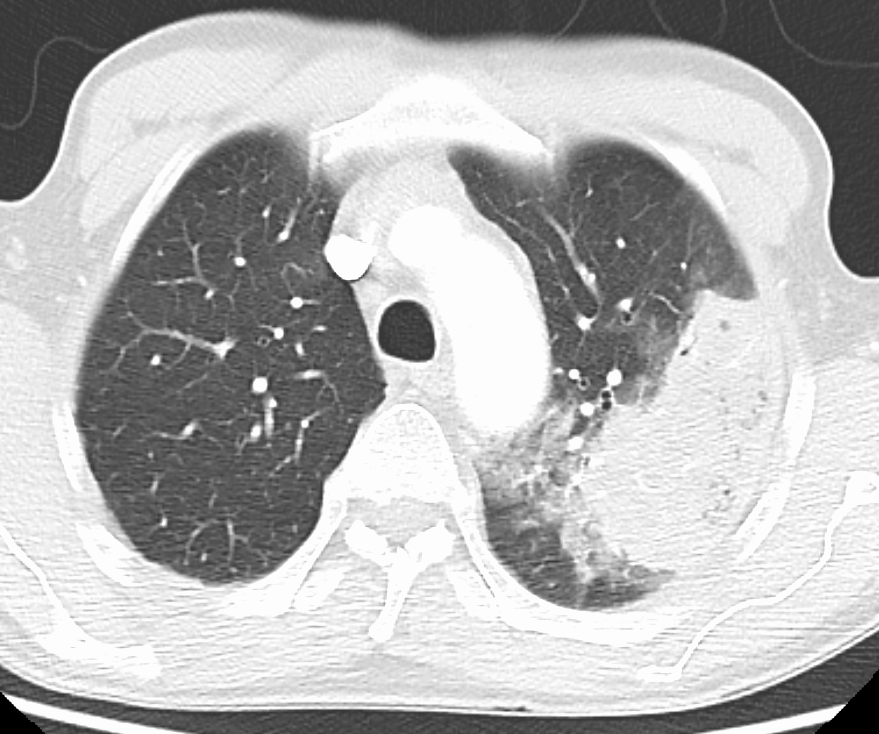

흉부 방사선 사진은 폐렴 진단에 흔히 사용된다.[141] 경증 환자는 잠재적 합병증이 있거나, 치료에 호전되지 않거나, 원인이 불확실한 경우에만 영상 검사가 필요하다.[141][65] 입원이 필요할 정도로 중증인 경우 흉부 방사선 사진이 권장된다.[65] 방사선 소견이 항상 질병의 중증도와 일치하지는 않으며, 세균성과 바이러스성 감염을 확실하게 구분하지 못한다.[141]

폐렴의 X선 사진 소견은 섬엽 폐렴, 세기관지 폐렴, 소엽 폐렴, 간질성 폐렴으로 분류할 수 있다.[66] 세균성, 급성 폐렴은 고전적으로 폐 분절엽 하나의 폐 실질 침윤을 보이는데, 이를 섬엽 폐렴이라고 한다.[72] 그러나 소견은 다양할 수 있으며, 다른 유형의 폐렴에서는 다른 양상이 흔하다.[72] 흡인성 폐렴은 주로 폐 아래쪽과 오른쪽에 양측성 음영으로 나타날 수 있다.[72] 바이러스성 폐렴의 X선 사진은 정상, 과팽창, 양측성 반점, 또는 섬엽 폐렴과 유사한 폐 실질 침윤으로 나타날 수 있다.[72] 특히 탈수가 있는 경우 질병 초기에는 방사선학적 소견이 없거나, 비만 또는 폐 질환 병력이 있는 사람은 해석하기 어려울 수 있다.[140] 흉막 삼출과 같은 합병증도 흉부 방사선 사진에서 발견될 수 있다. 측면 흉부 방사선 사진은 폐 실질 침윤과 흉막 삼출 진단 정확도를 높일 수 있다.[78]

CT 스캔은 불확실한 경우 추가 정보를 제공할 수 있으며,[72] 흉부 방사선 사진이 불분명한 경우(예: 만성 폐쇄성 폐 질환에서 숨겨진 폐렴) 더 자세한 정보를 제공할 수 있다. 치료에 반응하지 않는 사람들의 폐색전증과 진균성 폐렴을 배제하고, 폐농양을 검출하는 데 사용될 수 있다.[78] 그러나 CT 스캔은 비용이 더 비싸고, 방사선량이 더 높으며, 병상 옆에서 시행할 수 없다.[78]